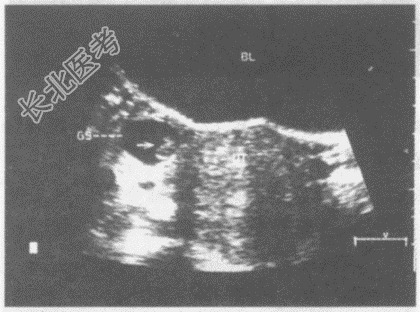

- 单项选择题临床资料:女性患者, 30岁,自述停经46天。阴道不规则出血6天。

化验检查: 尿妊娠试验阳性。

超声综合描述:子宫形态饱满, 回声均匀,内膜厚度1.4cm, 宫腔内未见胎囊。右附件区见环状无回声,内见胎芽及胎心搏动(箭头所指)。

超声提示:  A、卵巢囊肿扭转

B、盆腔炎

C、右输卵管异位妊娠

D、子宫角部妊娠

E、右卵巢异位妊娠